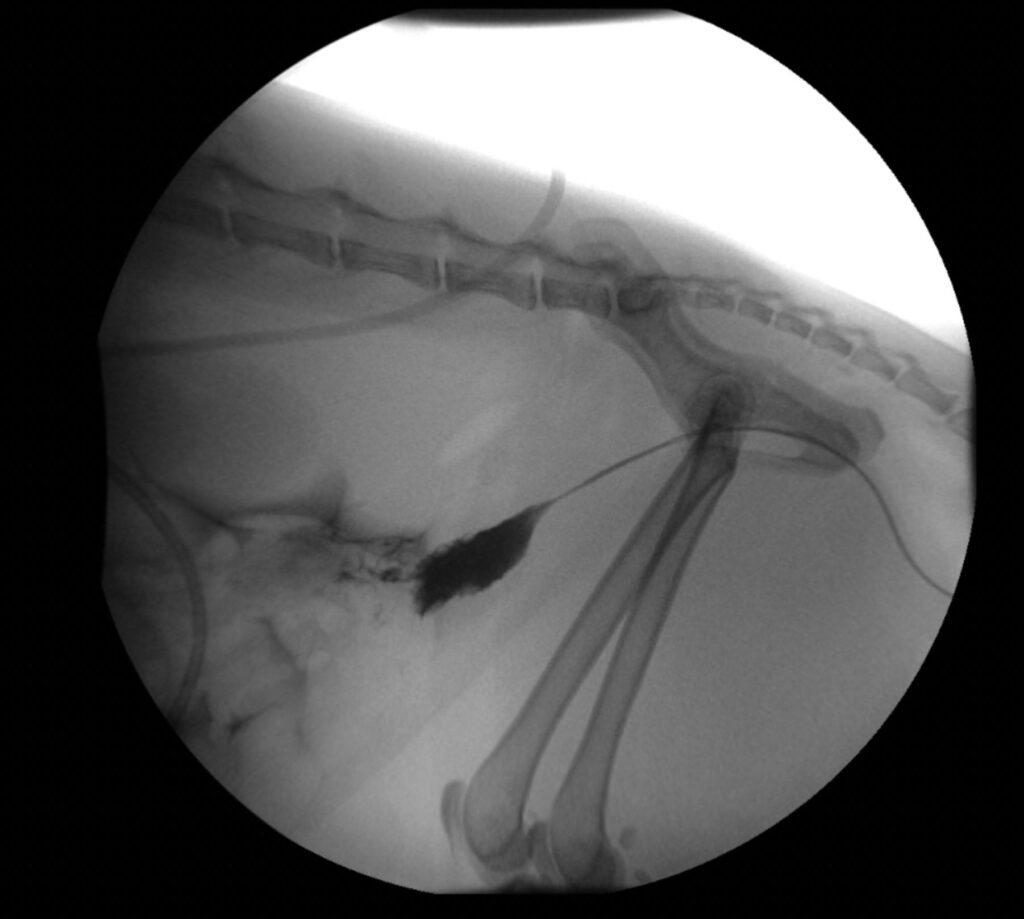

Fluoroscopy

Fluoroscopy is a non-invasive radiographic study that allows for real-time imaging using x-rays.

Some examples of how fluoroscopy is used include:

- swallowing, esophageal and gastrointestinal function and motility

- tracheal collapse

- orthopedic implant placement

- urogenital disease

- interventional procedures for heart, urinary or liver disease